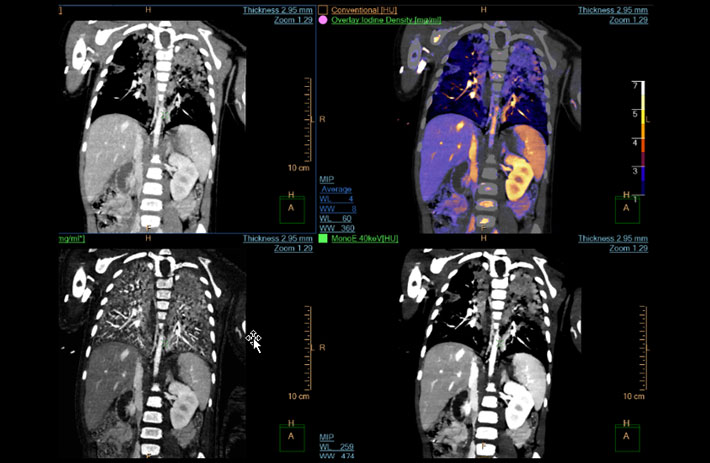

Mit dem Spektral-Detektor-CT werden Spektraldaten automatisch bei jedem Scan erfasst. Die Informationen stehen jederzeit auf der Scankonsole, der CT-Workstation sowie an jedem PACS-Arbeitsplatz zur Verfügung, sodass es nicht notwendig ist, den Patienten erneut zu scannen, bspw. wenn initial zufällige Anomalien festgestellt wurden. Dadurch profitieren Anwender durch eine höhere Diagnosesicherheit und weniger Nachuntersuchungen auf anderen bildgebenden Systemen. Unsere Fallsammlung zeigt, welchen klinischen Mehrwert der Spektral-Detektor-CT in unterschiedlichsten Anwendungsbereichen in der klinischen Routine bringt. Jede Woche gehen neue Fälle live.